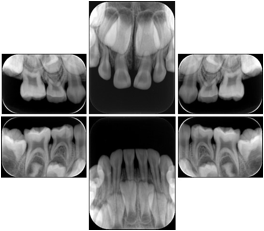

Intra-oral radiography typically involves acquisition of multiple images of various parts of the dentition. Many digital radiographic systems offer customized templates that are used for displaying the images in a study on the screen. These templates may also be referred to as mounts or view sets. The Structured Display Object represents a standard method of encoding and exchanging the layout and intended display of Structured Displays. A structured display object created in this manner could be stored with a study and exchanged with images to allow for complete reproduction of the original exam.

In most standard cases, images are oriented in structured layouts. These structured displays are useful to be shared between providers for reference purposes.

Table OO.1.1-1 shows structured display standard templates, where Viewset ID is based on the Japanese Society for Oral and Maxillofacial Radiology (JSOMR) classification provided by JIRA (Japan Medical Imaging and Radiological Systems Industries Association, www.jira-net.or.jp). Expected or typical teeth to be imaged location, region and designation codes are based on ISO 3950-2010, Dentistry - Designation system for teeth and areas of the oral cavity. For all the hanging protocols listed in OO.1.1-1, the value to use for Hanging Protocol Creator (0072,0008) is "JSOMR" and the value to use for Hanging Protocol Name (0072,0002) does not include "JSOMR" (e.g., "DL-S001A", not "JSOMR DL-S001A").